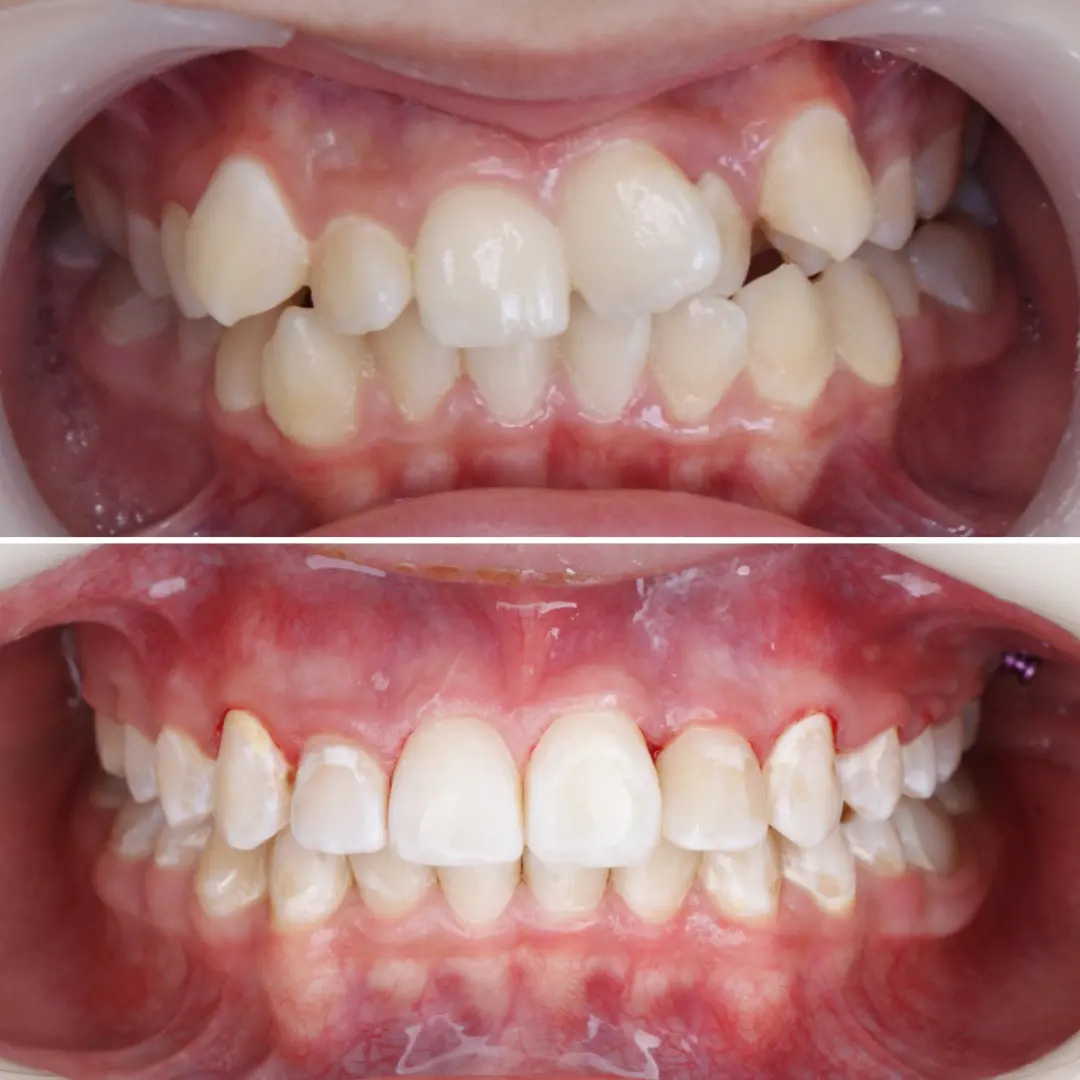

✔Глубокий прикус, дистальный прикус с пространством (щелью) между верхними и нижними резцами, скученное положение зубов, заблокированное нёбное положение верхнего левого зуба ✔Лечение на металлической самолигирующей системе Damon

✔Пациент, 12,5 лет на момент старта ✔Общий срок лечения 18 месяцев ✔Брекеты Damon Q ✔Дистальный, перекрестный, глубокий прикус, смещение нижней челюсти, несоответствие средних линий и сужение зубных рядов, скученность зубов, недостаток места для верхних клыков